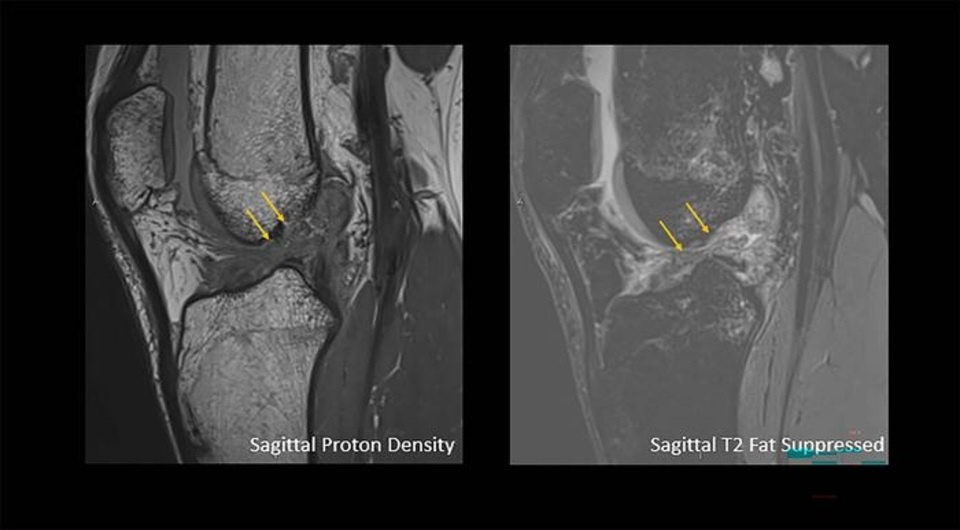

Ali Ghasemi et al. / RSNA, 2025

Рентгенологи проанализировали результаты 13549 магнитно-резонансных томограмм коленных суставов пациентов, жалующихся на боль в коленях, и выявили достоверную разницу в частоте различных травм между мужчинами и женщинами. Повреждение передней крестообразной связки (изолированный разрыв или разрыв вместе с повреждением мениска) значительно чаще наблюдается у мужчин во всех возрастных группах (р = 0,001). Доклад об исследовании представлен на Ежегодном собрании Радиологического общества Северной Америки.